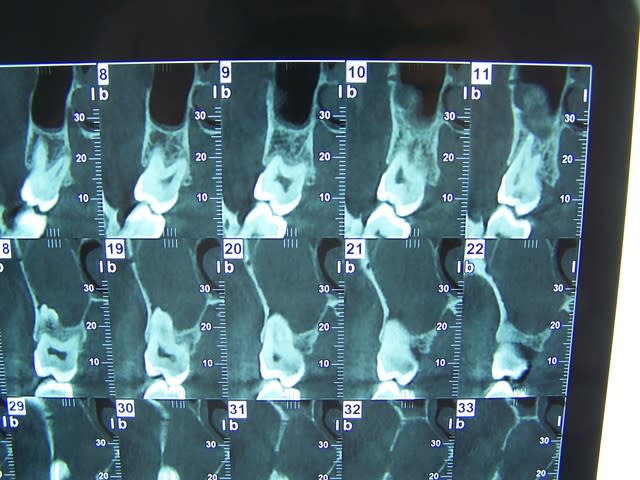

Tu as bien fait pour le scanner. Il faut commencer par ca .

Perso ce qui me heurte dans la radio c'est la difference de volume entre les sinus droit et gauche.

Apres un kyste, un CE ou je ne sais quoi peut importe

Pas de coque du plancher sinusien visible sur les rx, à priori énorme destruction osseuse depuis 17 jusque 14, avec également masse radio dense grise de la taille d'une balle de ping pong mais de forme alongée.

J'ai bien peur devant le tableau que la notion de cancer ne soit pas facilement écartable, surtout si douleurs d'apparition rapides.

je viens de tel au radiologue: " le kyste est énorme et englobe 17 16 et 15, mais les corticales semblent préservées".

sur la première pano, on voit une grosse image radio claire de 17 à 14 a priori. ça serait intéressant de voir deux ou trois coupes du scanner ou le cone beam, mais je pense à un banal kyste d'origine dentaire très probablement en rapport avec la 16 d'autant que l'extension semble se faire en distal.

le kyste peut très bien refouler et respecter le plancher sinusien, dans ce cas les cones sont dans le kyste.